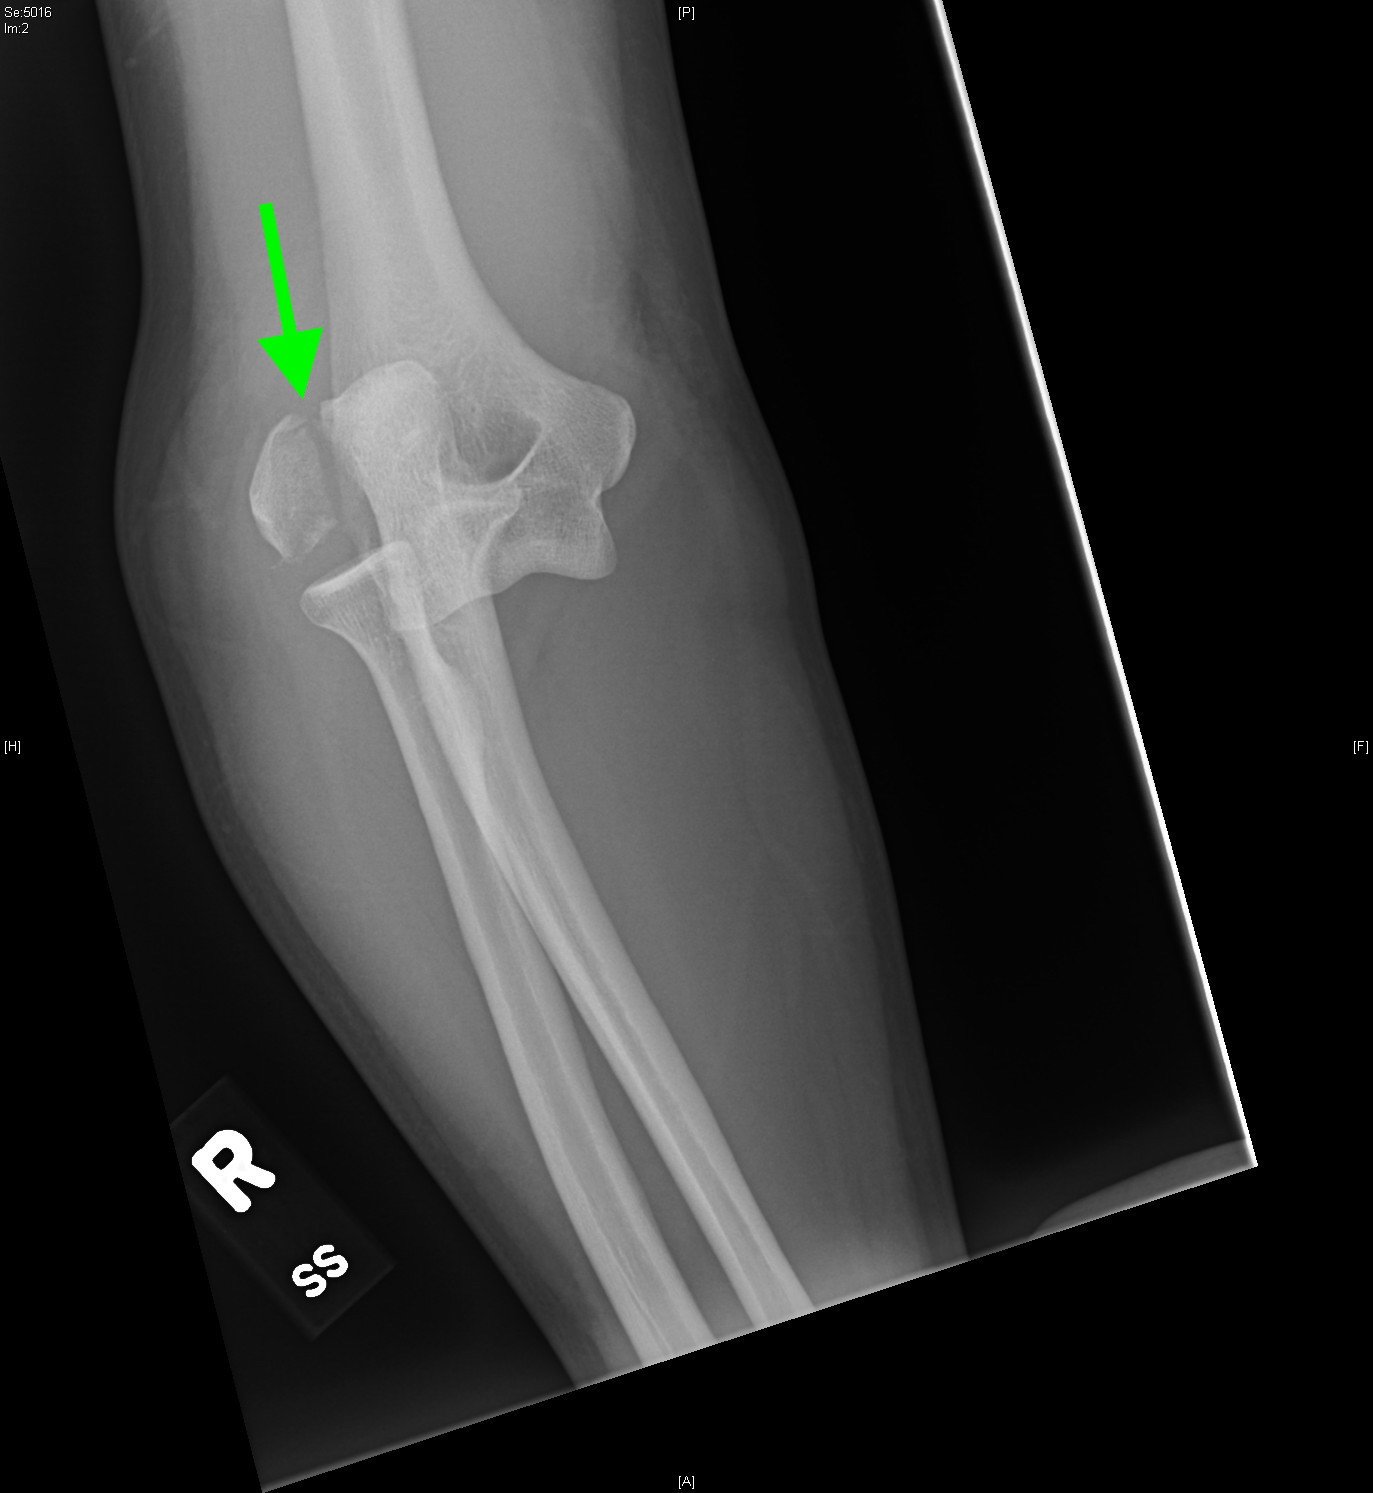

Radiographs of the right elbow revealed an acute fracture through the lateral epicondyle with dislocation of the radial head inferiorly. Radiographs of the left elbow revealed a slightly angulated fracture through the lateral epicondyle.

Given the patient’s bilateral condylar fractures, orthopedics was consulted and recommended reduction of the dislocated right radial head with bilateral splinting. Post-reduction films revealed successful reduction and patient was neurovascularly intact before and after the procedure. The patient was discharged with instructions for short interval follow up in the orthopedics clinic to discuss the necessity for surgical management of the fractures.